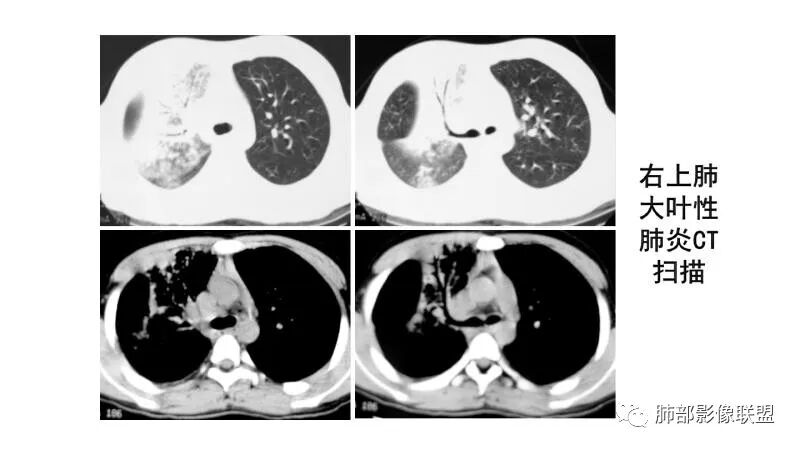

【每日晨读】 肺实变影之华山论剑

大叶性肺炎就是累及肺泡,然后沿着肺泡孔蔓延,不按叶段分布,跟支气管也没什么关系,是外朝内,不是内朝外吧?

大叶性肺炎,非节段分布,外朝内

大叶性肺炎一定受叶、段的局限。充其量周围有一些蔓延出来。肺链,金葡都是。金葡和曲霉的一个鉴别点:一个从内向外,一个从外向内。3型曲霉-农村包围城市。金葡-城市向农村发展。

2)沿胸膜下分布趋势(不同于大叶性肺炎的肺叶“造型”)。